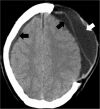

Malignant stroke occurs in a subgroup of patients suffering from ischemic cerebral infarction and is characterized by neurological deterioration due to progressive edema, raised intracranial pressure, and cerebral herniation. Decompressive craniectomy (DC) is a surgical technique aiming to open the "closed box" represented by the non-expandable skull in cases of refractory intracranial hypertension. It is a valuable modality in the armamentarium to treat patients with malignant stroke: the life-saving effect has been proven for both supratentorial and infratentorial DC in virtually all age groups. This leaves physicians with the difficult task to decide who will require early or preemptive surgery and who might benefit from postponing surgery until clear evidence of deterioration evolves. Together with the patient's relatives, physicians also have to ascertain whether the patient will have acceptable disability and quality of life in his or her presumed perception, based on preoperative predictions. This complex decision-making process can only be managed with interdisciplinary efforts and should be supported by continued research in the age of personalized medicine.